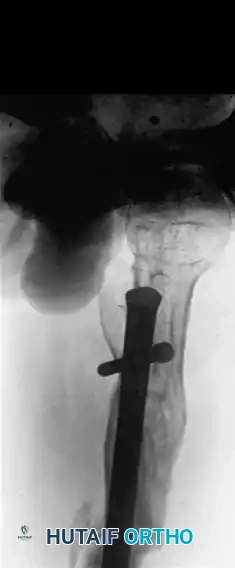

FIGURE 58-24 A: Anteroposterior radiograph demonstrating a malunion of a subtrochanteric fracture.

Image

FIGURE 58-24 B: Lateral radiograph of the same subtrochanteric malunion highlighting severe internal rotational deformity.